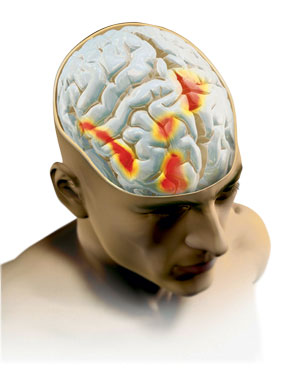

Úgy tűnik, hogy a placebo hatás a fejlődés egy kisebb vagy nagyobb mértékben, mindkét mechanizmusnak szerepe van, de lehet, hogy mivel lehet a hatása „bábuk” nem egy fikció, kitalált a beteg, és a tényleges folyamat, amely megváltoztatja az idegrendszer, a hormonális és immunrendszerre még. Segítségével MRI kutatók megállapították, hogy az agy a placebót kapó betegeknél, aktiválja számos területen, amelynek nagy része felelős a tudatos tevékenység.

Színezett piros agyi régiók aktiválódnak válaszul a placebo hatás (megnövelt aktivitás felszabadulásával összefüggő természetes endorfinok)